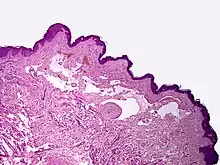

Microscopicamente, as vesículas em um linfangioma circunscrito são canais linfáticos dilatados expandindo a derme papilar. Eles podem ser associados com acantose e hiperqueratose. Há muitos canais na derme superior, muitas vezes se estendendo para o tecido subcutâneo (a camada mais profunda da derme, contendo gordura e tecido conjuntivo). Os vasos mais profundos têm grande calibre com paredes espessas que contêm musculatura lisa. O lúmen é preenchido com fluido linfático, mas muitas vezes contém glóbulos vermelhos, linfócitos, macrófagos, e neutrófilos. Os canais são revestidos com células endoteliais planas. O interstício tem muitas células linfóides e mostra evidência de fibroplasia (a formação de tecido fibroso). Nódulos (uma pequena massa de tecido ou agregação de células) em linfangiomas cavernosos são grandes canais, irregulares, na derme reticular e tecido subcutâneo que são revestidos por uma camada única de células endoteliais e uma camada incompleta de músculo liso. O estroma é constituído por tecido conjuntivo frouxo com uma grande quantidade de células inflamatórias. Estes tumores geralmente penetram a musculatura. O higroma cístico é histologicamente indistinguível de um linfangioma cavernoso. [7]